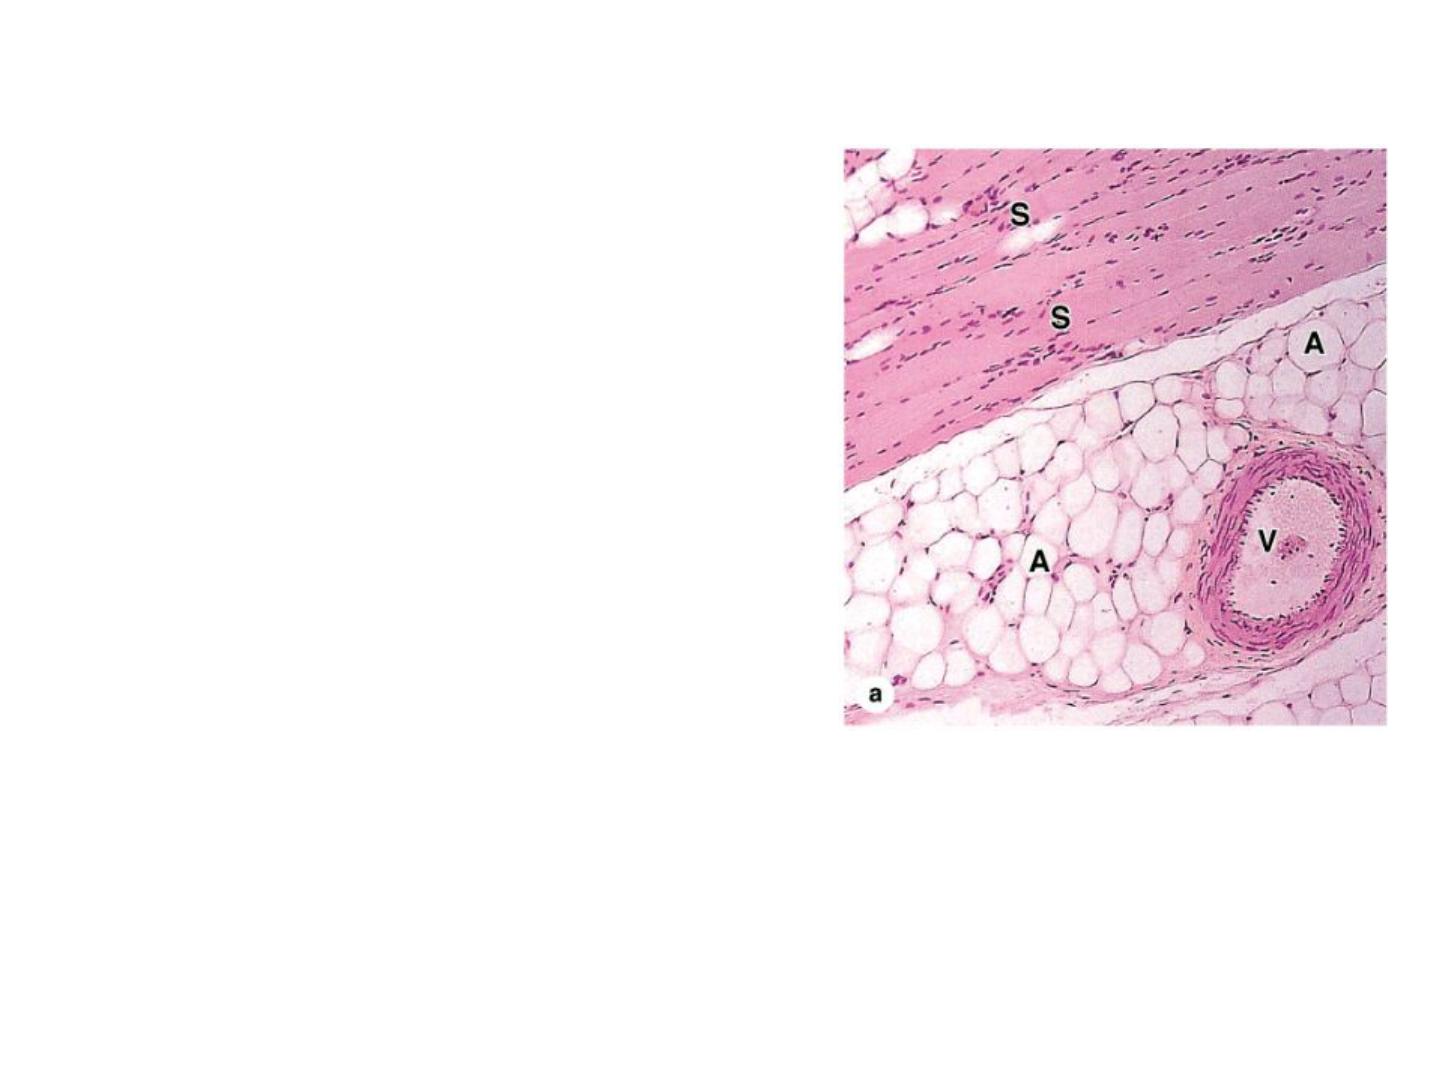

Adipose connective tissue:

is located throughout the body, adipose

tissue normally represents 15%-20% of the

body weight in men, somewhat more in

women about 20%-25%.

With a growing worldwide epidemic of

obesity and its associated health problems,

including

diabetes

and

heart

disease,

adipocytes and adipose tissue now constitute

a major area of medical research.

In this photomicrograph adipocytes (A)

are seen in the connective tissue

associated with a blood vessel (V) in

striated muscle (S). X100. H&E.